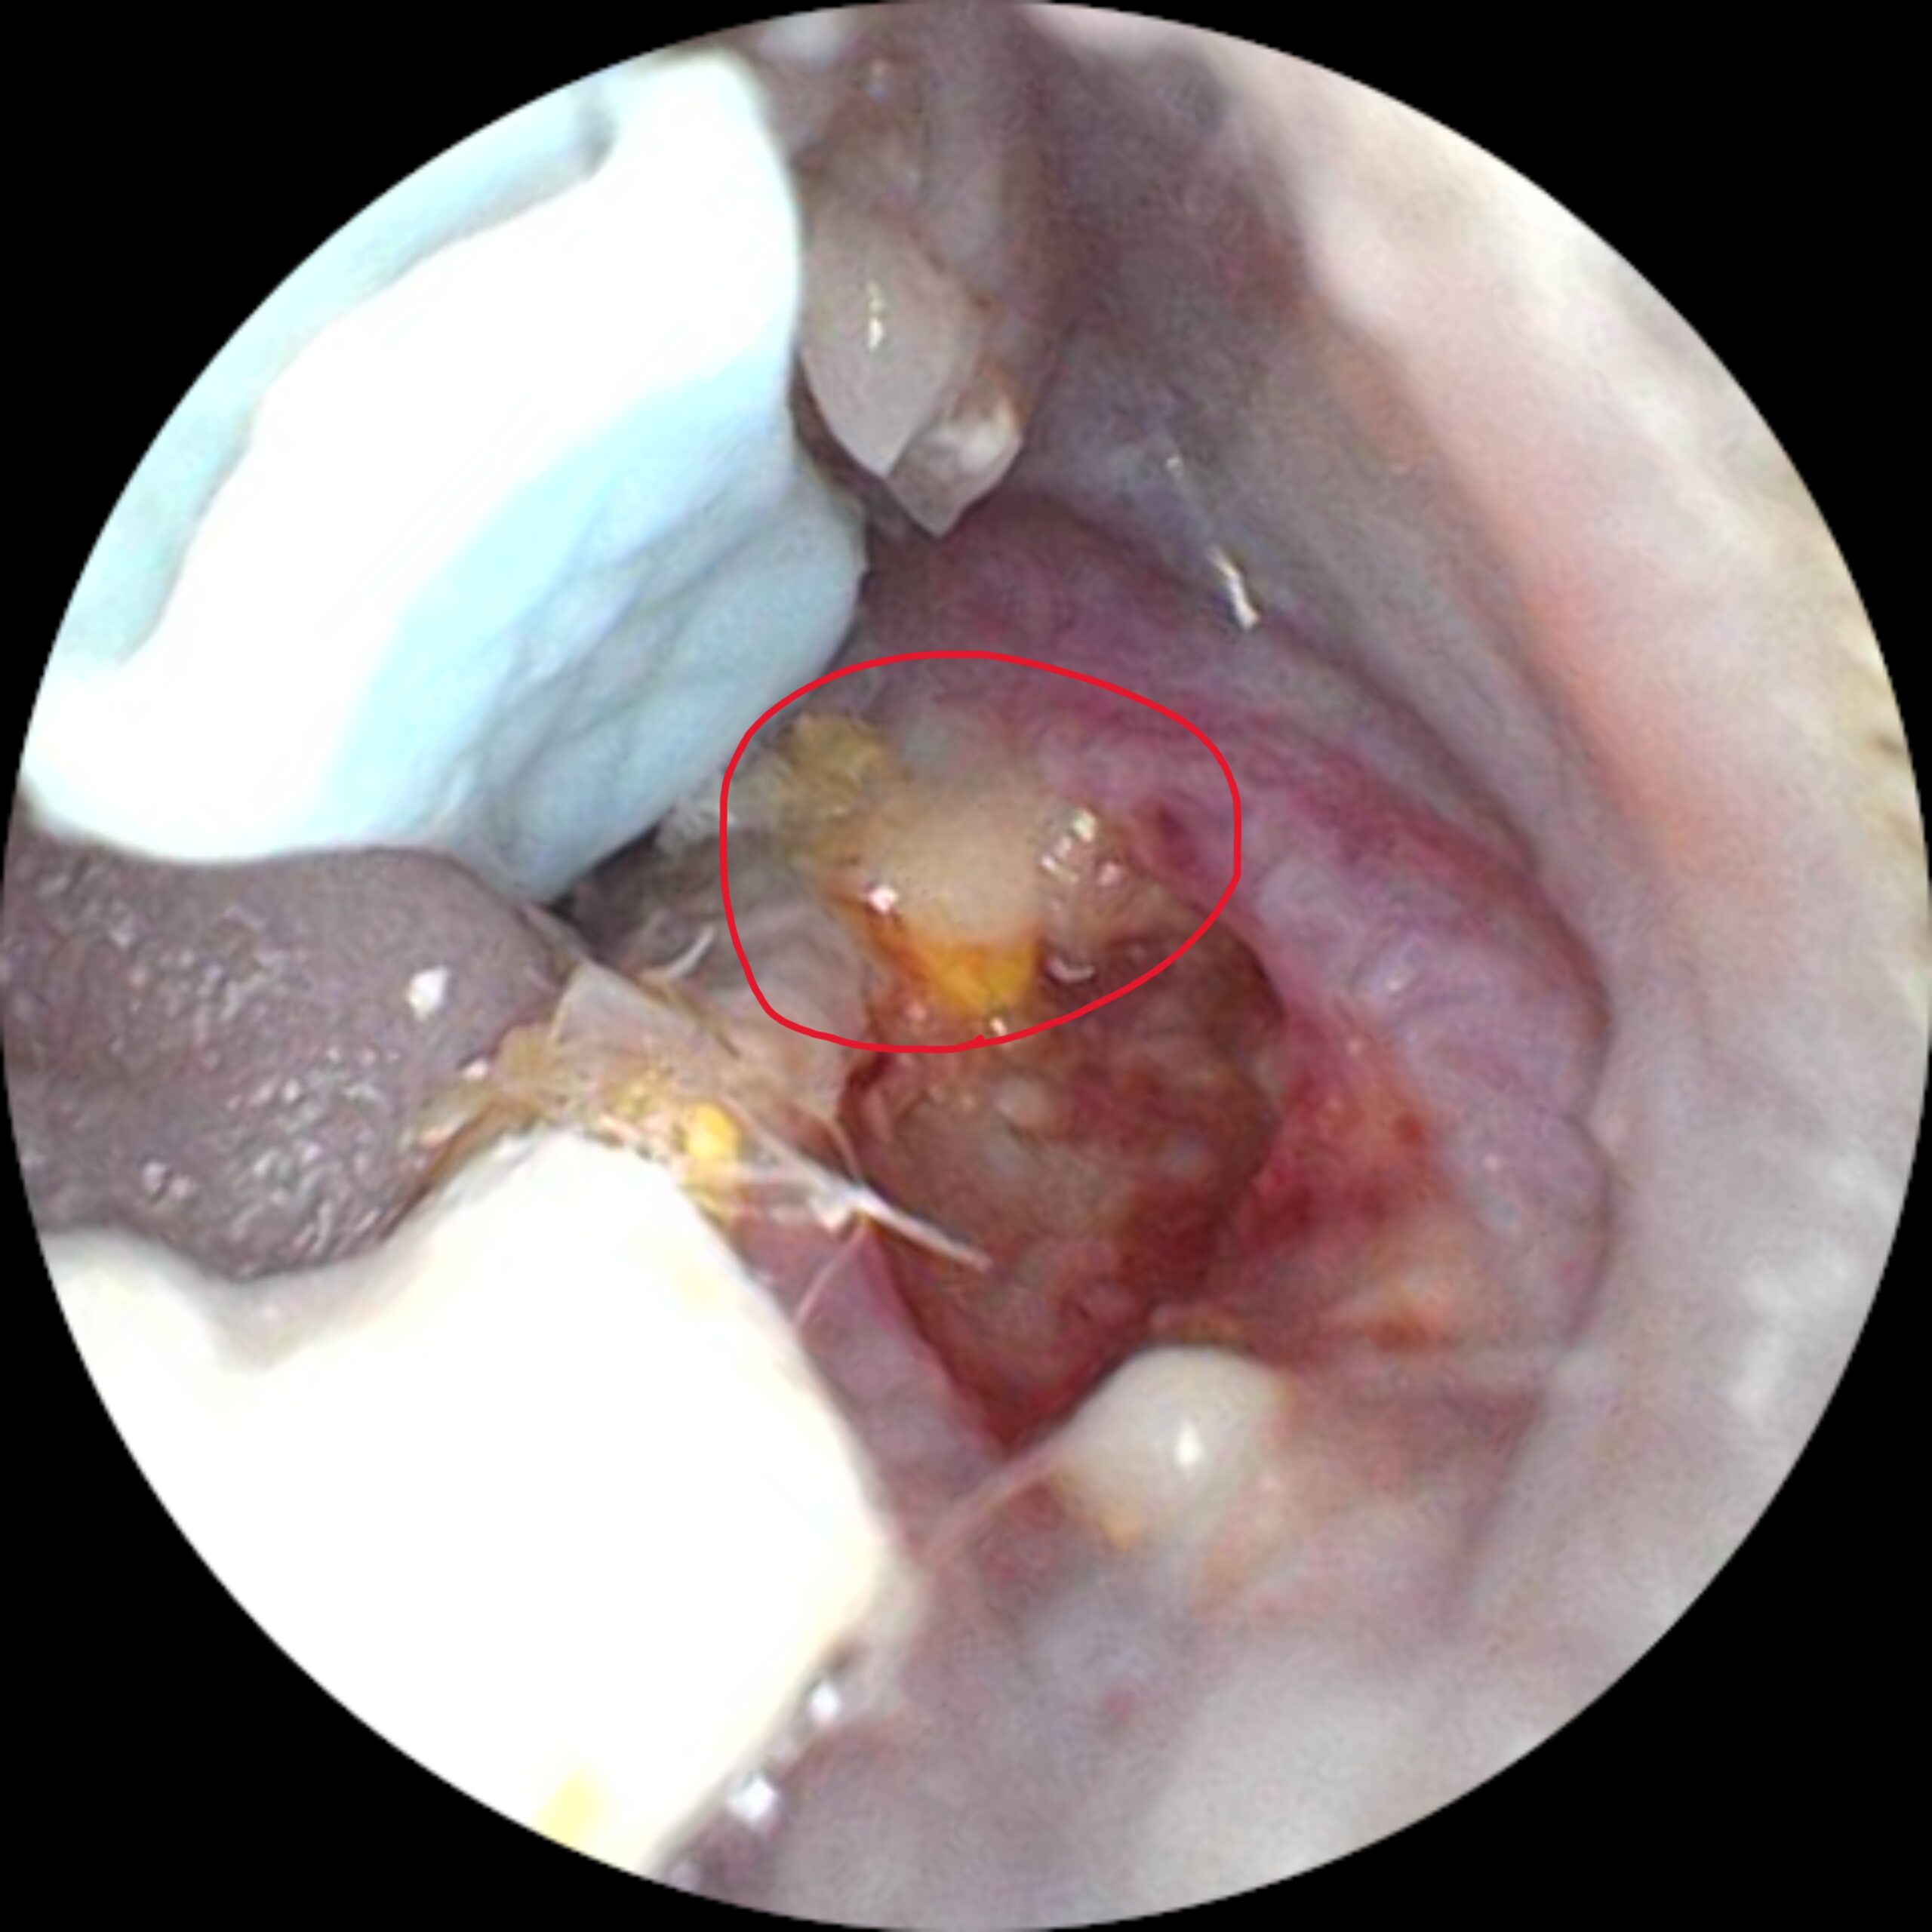

診断は、身体検査と視診・触診により顔や口周囲の腫脹の有無を確認することから始まります。口腔内の観察で歯の過伸長、欠損、膿の排出口(瘻管)などを確認しますが、フクロモモンガは非常に小さく、口腔内の観察が困難なため、麻酔下での精密検査が必要となる場合があります。

X線検査や口腔内視診によって、歯根部の感染範囲や骨の融解・変形の程度を評価します。膿の一部を採取し、細菌培養検査および感受性試験を行うことで、効果的な抗菌薬を選択することができます。

治療の基本は、感染源となっている歯根および膿瘍の除去です。外科的に膿瘍を開放して排膿し、膿や壊死組織を徹底的に除去します。感染歯が原因の場合は、抜歯を行うことが根本治療につながります。